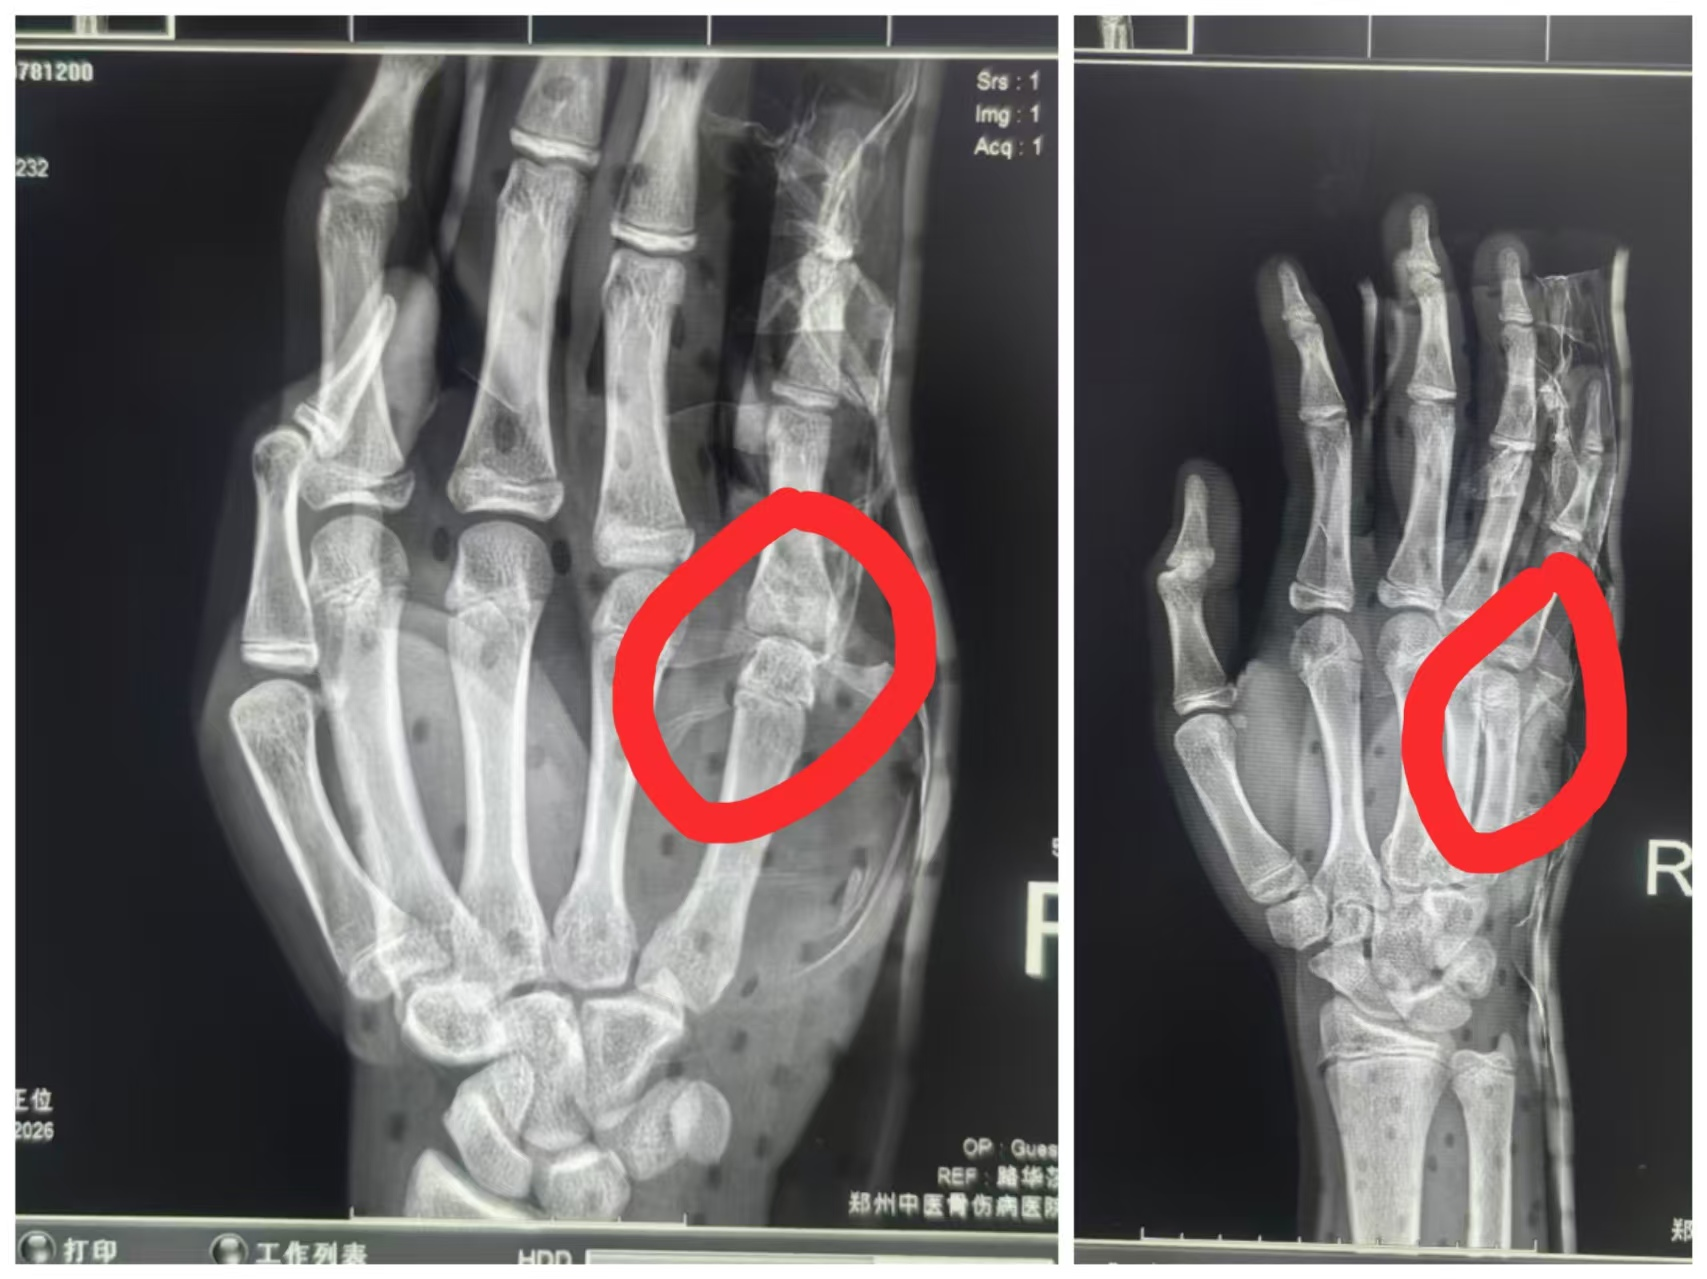

进一步检查发现,男孩右手第五掌骨远端肿胀极为明显,局部压痛和叩击痛反应强烈,甚至能触及骨擦感,掌指关节呈屈曲畸形,活动完全受限。不过幸运的是,右手末梢血运和感觉均正常。影像学检查也给出了明确结果:右手正斜位 X 线片显示右手第五掌骨颈骨折,骨折端向背侧成角畸形,对位对线情况极差。

路华莎主任即时评估发现,复位后右手第五掌骨肿胀明显减轻,畸形消失不见,局部压痛较之前大幅缓解;掌指关节活动度初步恢复,且无反常活动。影像学复查结果更是令人欣喜:即刻进行的右手正斜位 X 线片显示,右手第五掌骨骨折端对位对线良好,成角畸形完全矫正。